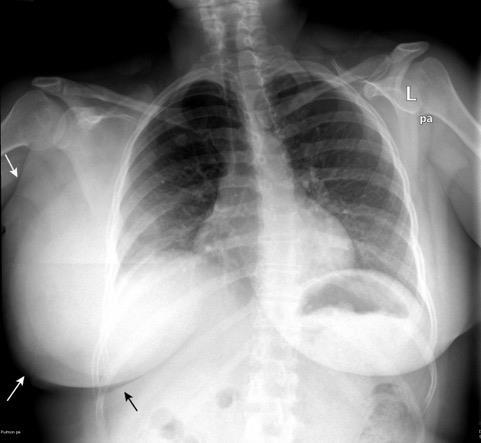

Tumor desmoide derecho. Recidiva.

Tumor maligno. 0,2% de los tumores de mama.

Ocurren en 10% de los implantes de mama.

En los 3 años después del implante.

(Dudas sobre el dato)

Kilmartin C et al. Desmoid Tumor and Implant-Based Breast Reconstruction. Case Rep Oncol. 2023